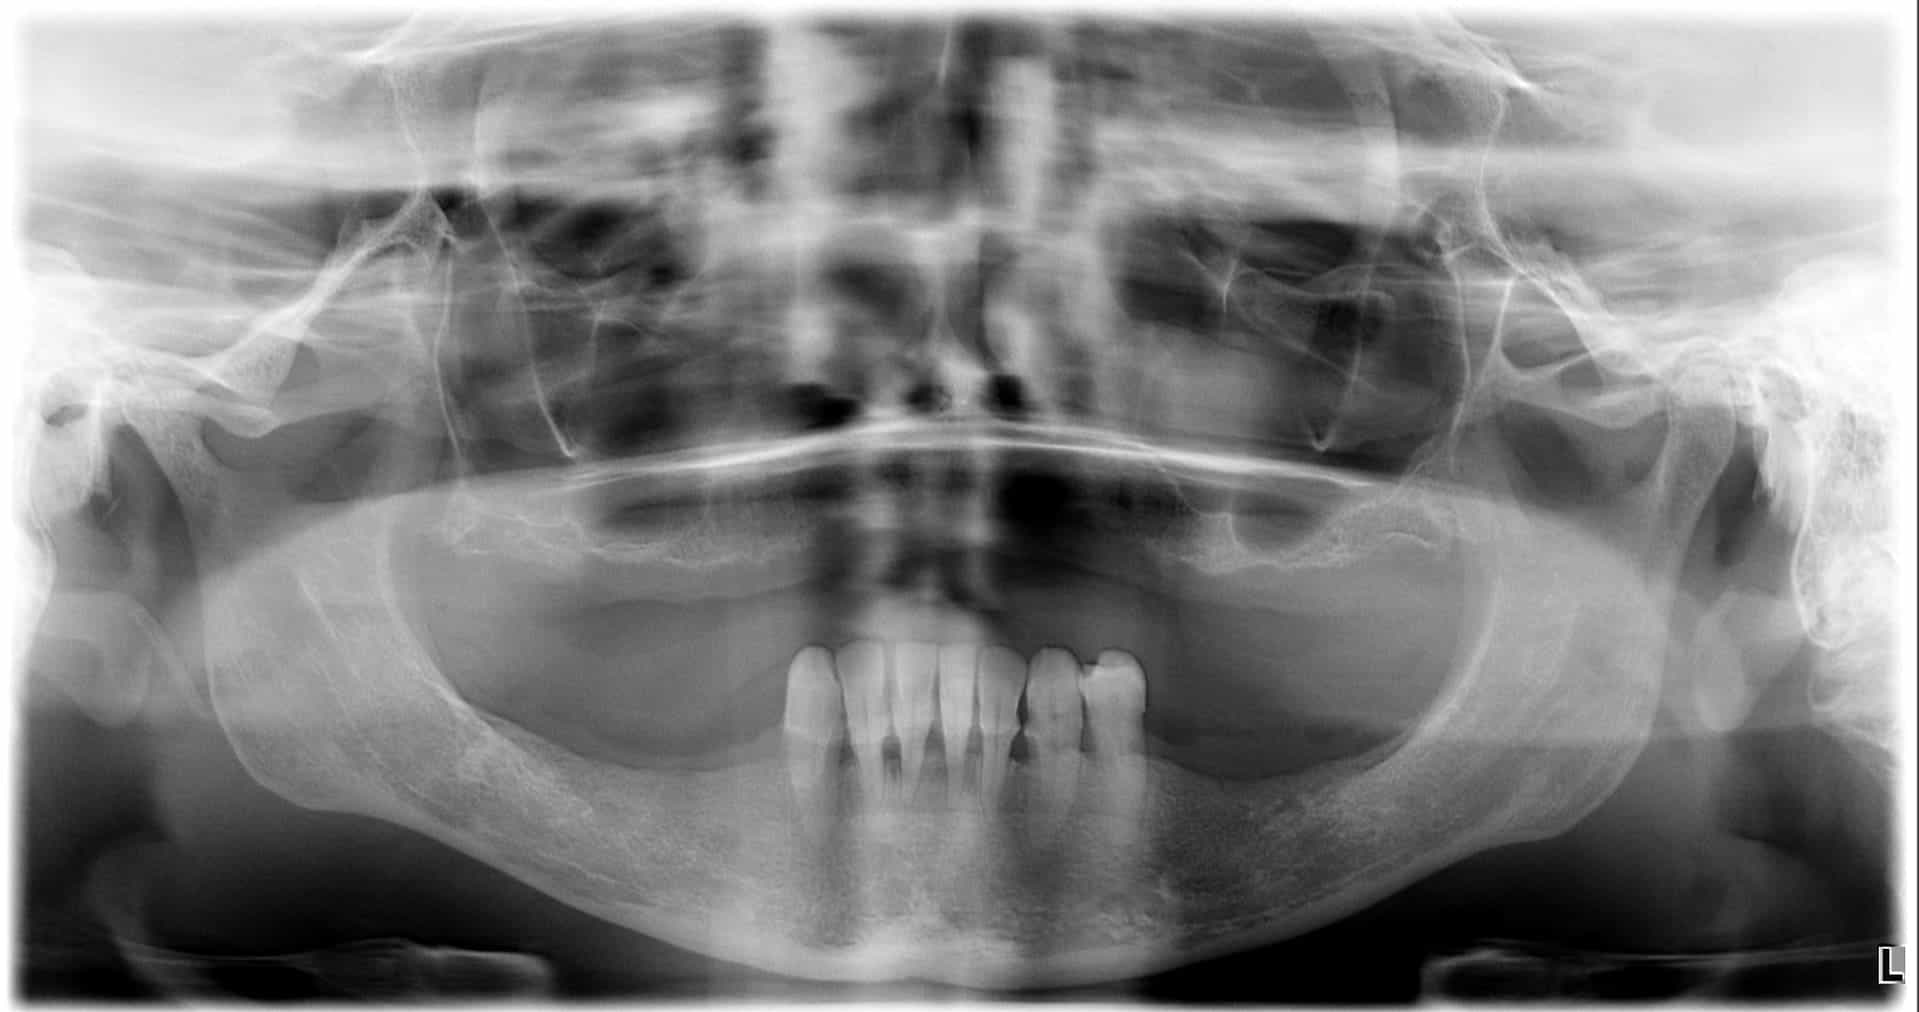

Casi clinici

Paziente 4

< Prima

Dopo >